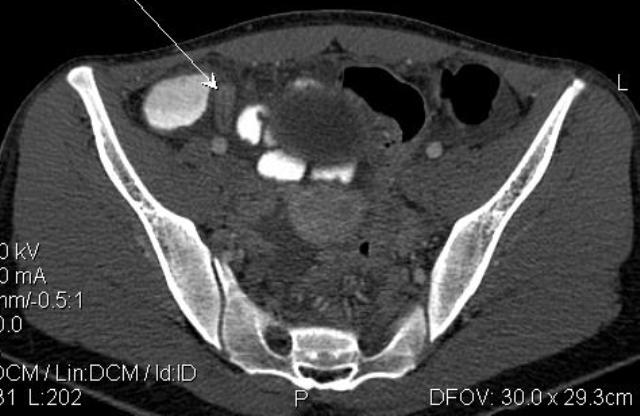

- Острый аппендицит, КТ MPR coronal

- AA Cor.jpg (18.44 КБ) 1340 просмотров